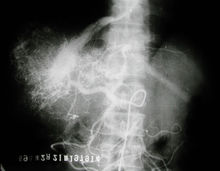

肝臟所接受血液的1/4由肝動(dòng)脈輸送,肝動(dòng)脈由心臟逐級(jí)分支而

來(lái),另3/4的血液由引流腸道血液的門靜脈運(yùn)送而來(lái),由腸道引流來(lái)的血液充滿已被消化的食物待肝臟予以處理。

血液經(jīng)肝靜脈離開(kāi)肝臟,此時(shí)肝動(dòng)脈和門靜脈的血液已混為一體,肝靜脈匯入體內(nèi)最大的靜脈--下腔靜脈,后者將血液引入心臟。